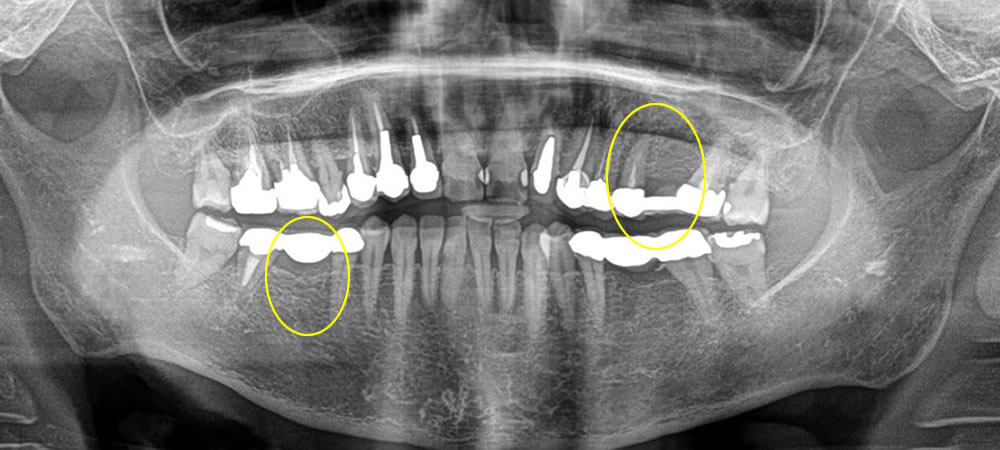

破折歯を抜歯即時埋入インプラントで治療した症例

年齢

50代

性別

女性

症例を見る